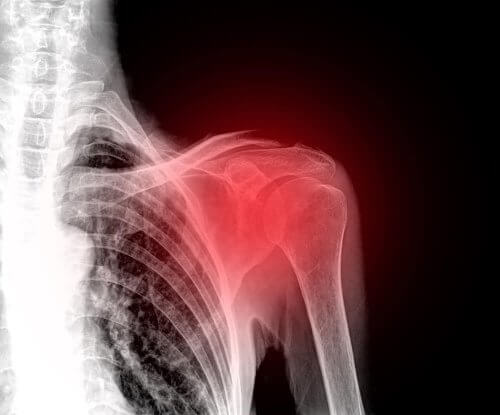

تمزق الكفة المدورة من الإصابات الشائعة بين البالغين والتي تصيب الكتفين. في الواقع، هذه الحالة هي أحد الأسباب الرئيسية لظهور آلام الكتف.

الكفة المدورة هي مجموعة من العضلات والأوتار التي تثبت عظام الكتف. وهي المسؤولة عن الحفاظ على استقرار المفصل والسماح له بتنفيذ جميع الحركات الممكنة بشكل طبيعي.

وللأسف، الكتف من أجزاء الجسم سهلة الضمور، وهو ما يؤدي عادةً إلى عدم الراحة. والإصابة في هذه المنطقة يمكن أن تكون مؤلمة ومعطلة جدًا. لذلك، نرغب اليوم في شرح كل ما تحتاج إلى معرفته بشأن حالة تمزق الكفة المدورة.

الأعراض التي تظهر تعتمد على حدة الإصابة. ولكن العرض الأكثر شيوعًا وظهورًا هو ألم الكتف. بجانب ذلك، تصبح جميع حركات هذا المفصل محدودة.

يعاني بعض المصابين من مشكلات أثناء النوم بشكل أساسي. في الواقع، يجد البعض النوم على الجانب المصاب أمرًا مستحيلًا تقريبًا. بالإضافة إلى أن المهمات البسيطة كتصفيف الشعر، ارتداء الملابس والاغتسال تصبح معقدة.